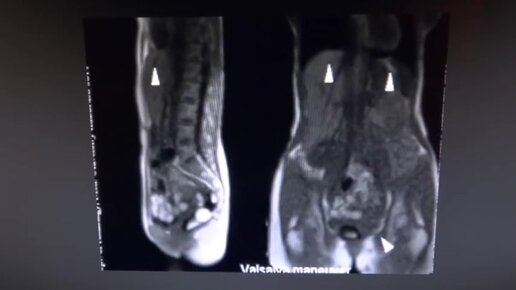

Дыхание тела на МРТ